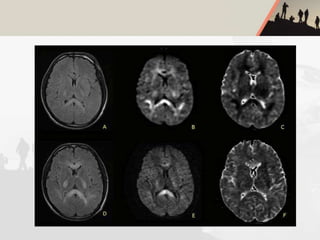

HIGH ALTITUDE CEREBRAL

OEDEMA(HACO)